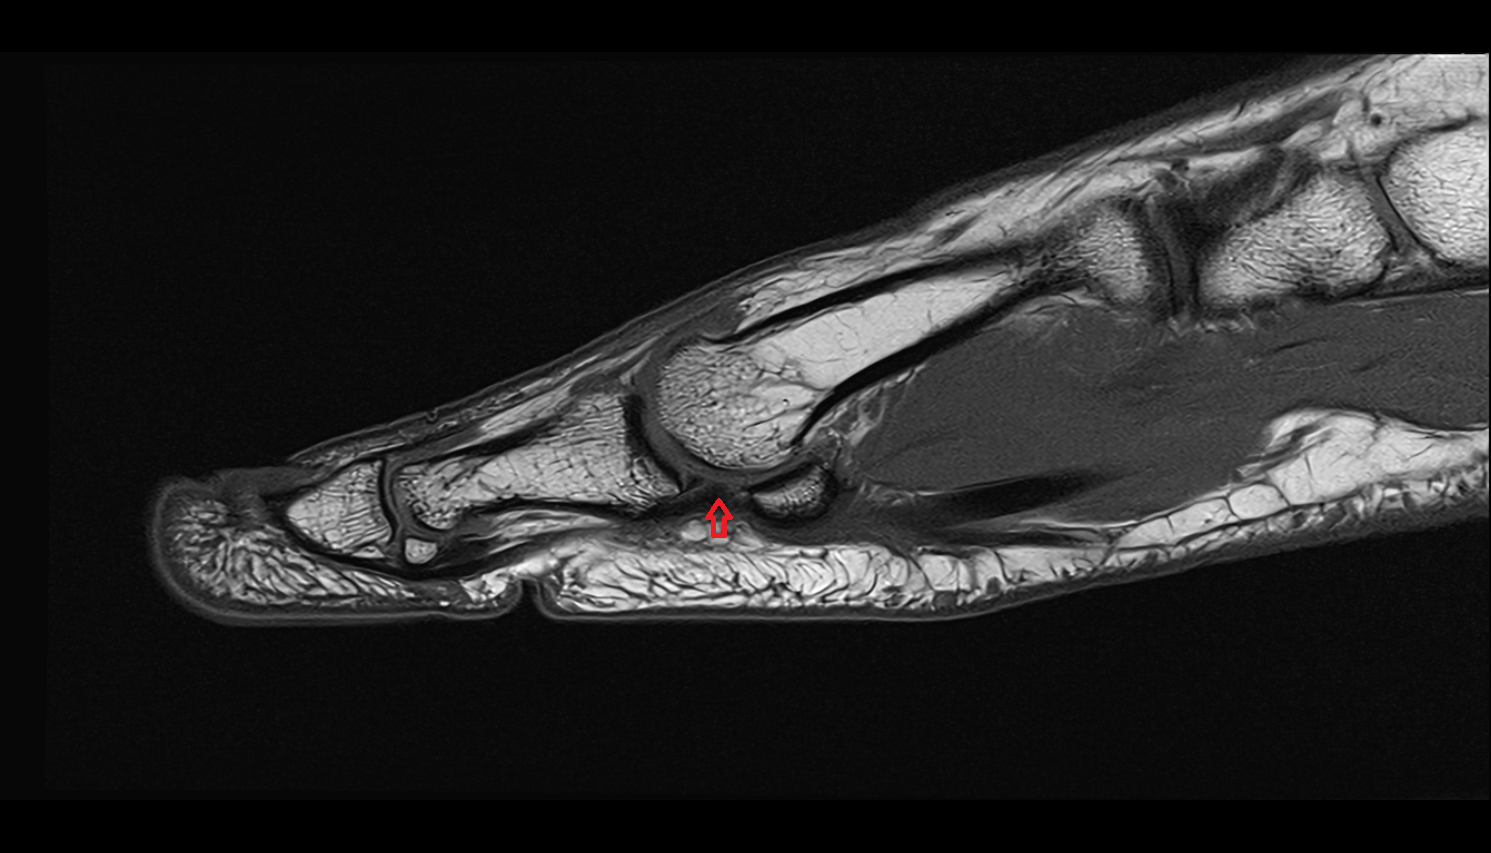

- Fetal ankle

- Fetal foot